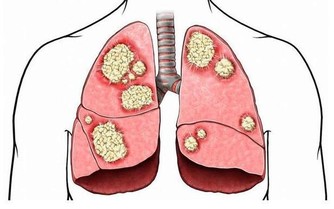

易感染(細菌、病毒、真菌),

易出現輕度的炎症(感冒、鼻炎、咽炎、扁桃體炎、皮炎等);